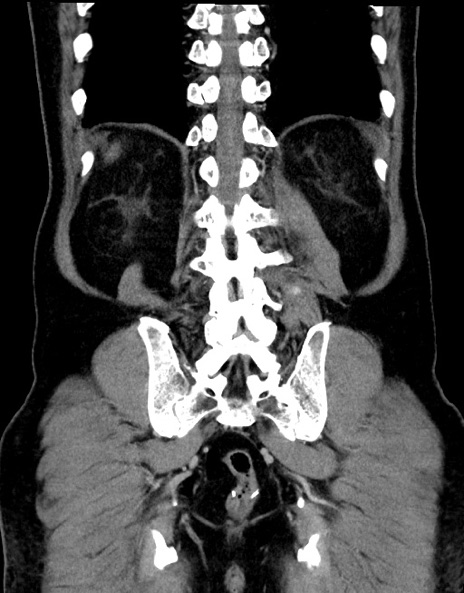

横断像

【症例】70歳代男性

【主訴】腹痛

【現病歴】今朝から腹痛あり。全体的に痛い。特に左上の方。排ガスが今日はない。冷や汗が出る。

【既往歴】直腸癌術後

【身体所見】左側腹部〜上腹部に圧痛あり。腹膜刺激症状明らかなではない。軽度反跳痛。左下腹部に術後瘢痕あり。

【データ】WBC 7700、CRP 0.02